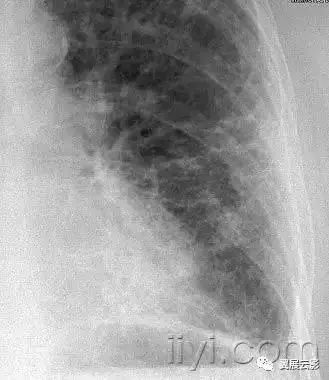

平片和CT:肺实变表现为肺实质密度的均匀一致性增高,导致肺血管和气道壁边缘不清。有时可见含气支气管征。只有在极少数的情况下,肺实变的密度变化有助于鉴别诊断,例如脂性肺炎是密度减低,胺碘酮中毒时密度增高。

图示为多灶性的肺实变。